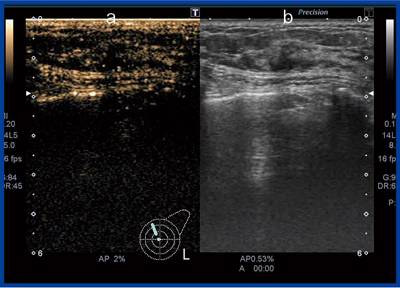

a:造影超音波,b:Bモード画像

Aplio 500とPLT-704SBT使用

Bモード画像で低エコー域をトレースし,造影超音波を行ったところ,クーパー靱帯に沿う流入血管がはっきり描出され,トレースした低エコー部やハローを越えて,周囲に広がる染影が確認できた。造影部分には実際に腫瘍の進展が確認されており,造影超音波が広がり診断にも有用なことを示唆する症例である。

Aplio 500とPLT-704SBT使用。